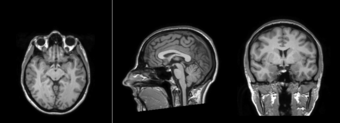

Atlas Image

Atlas Mask

Mask overlay on patient volume